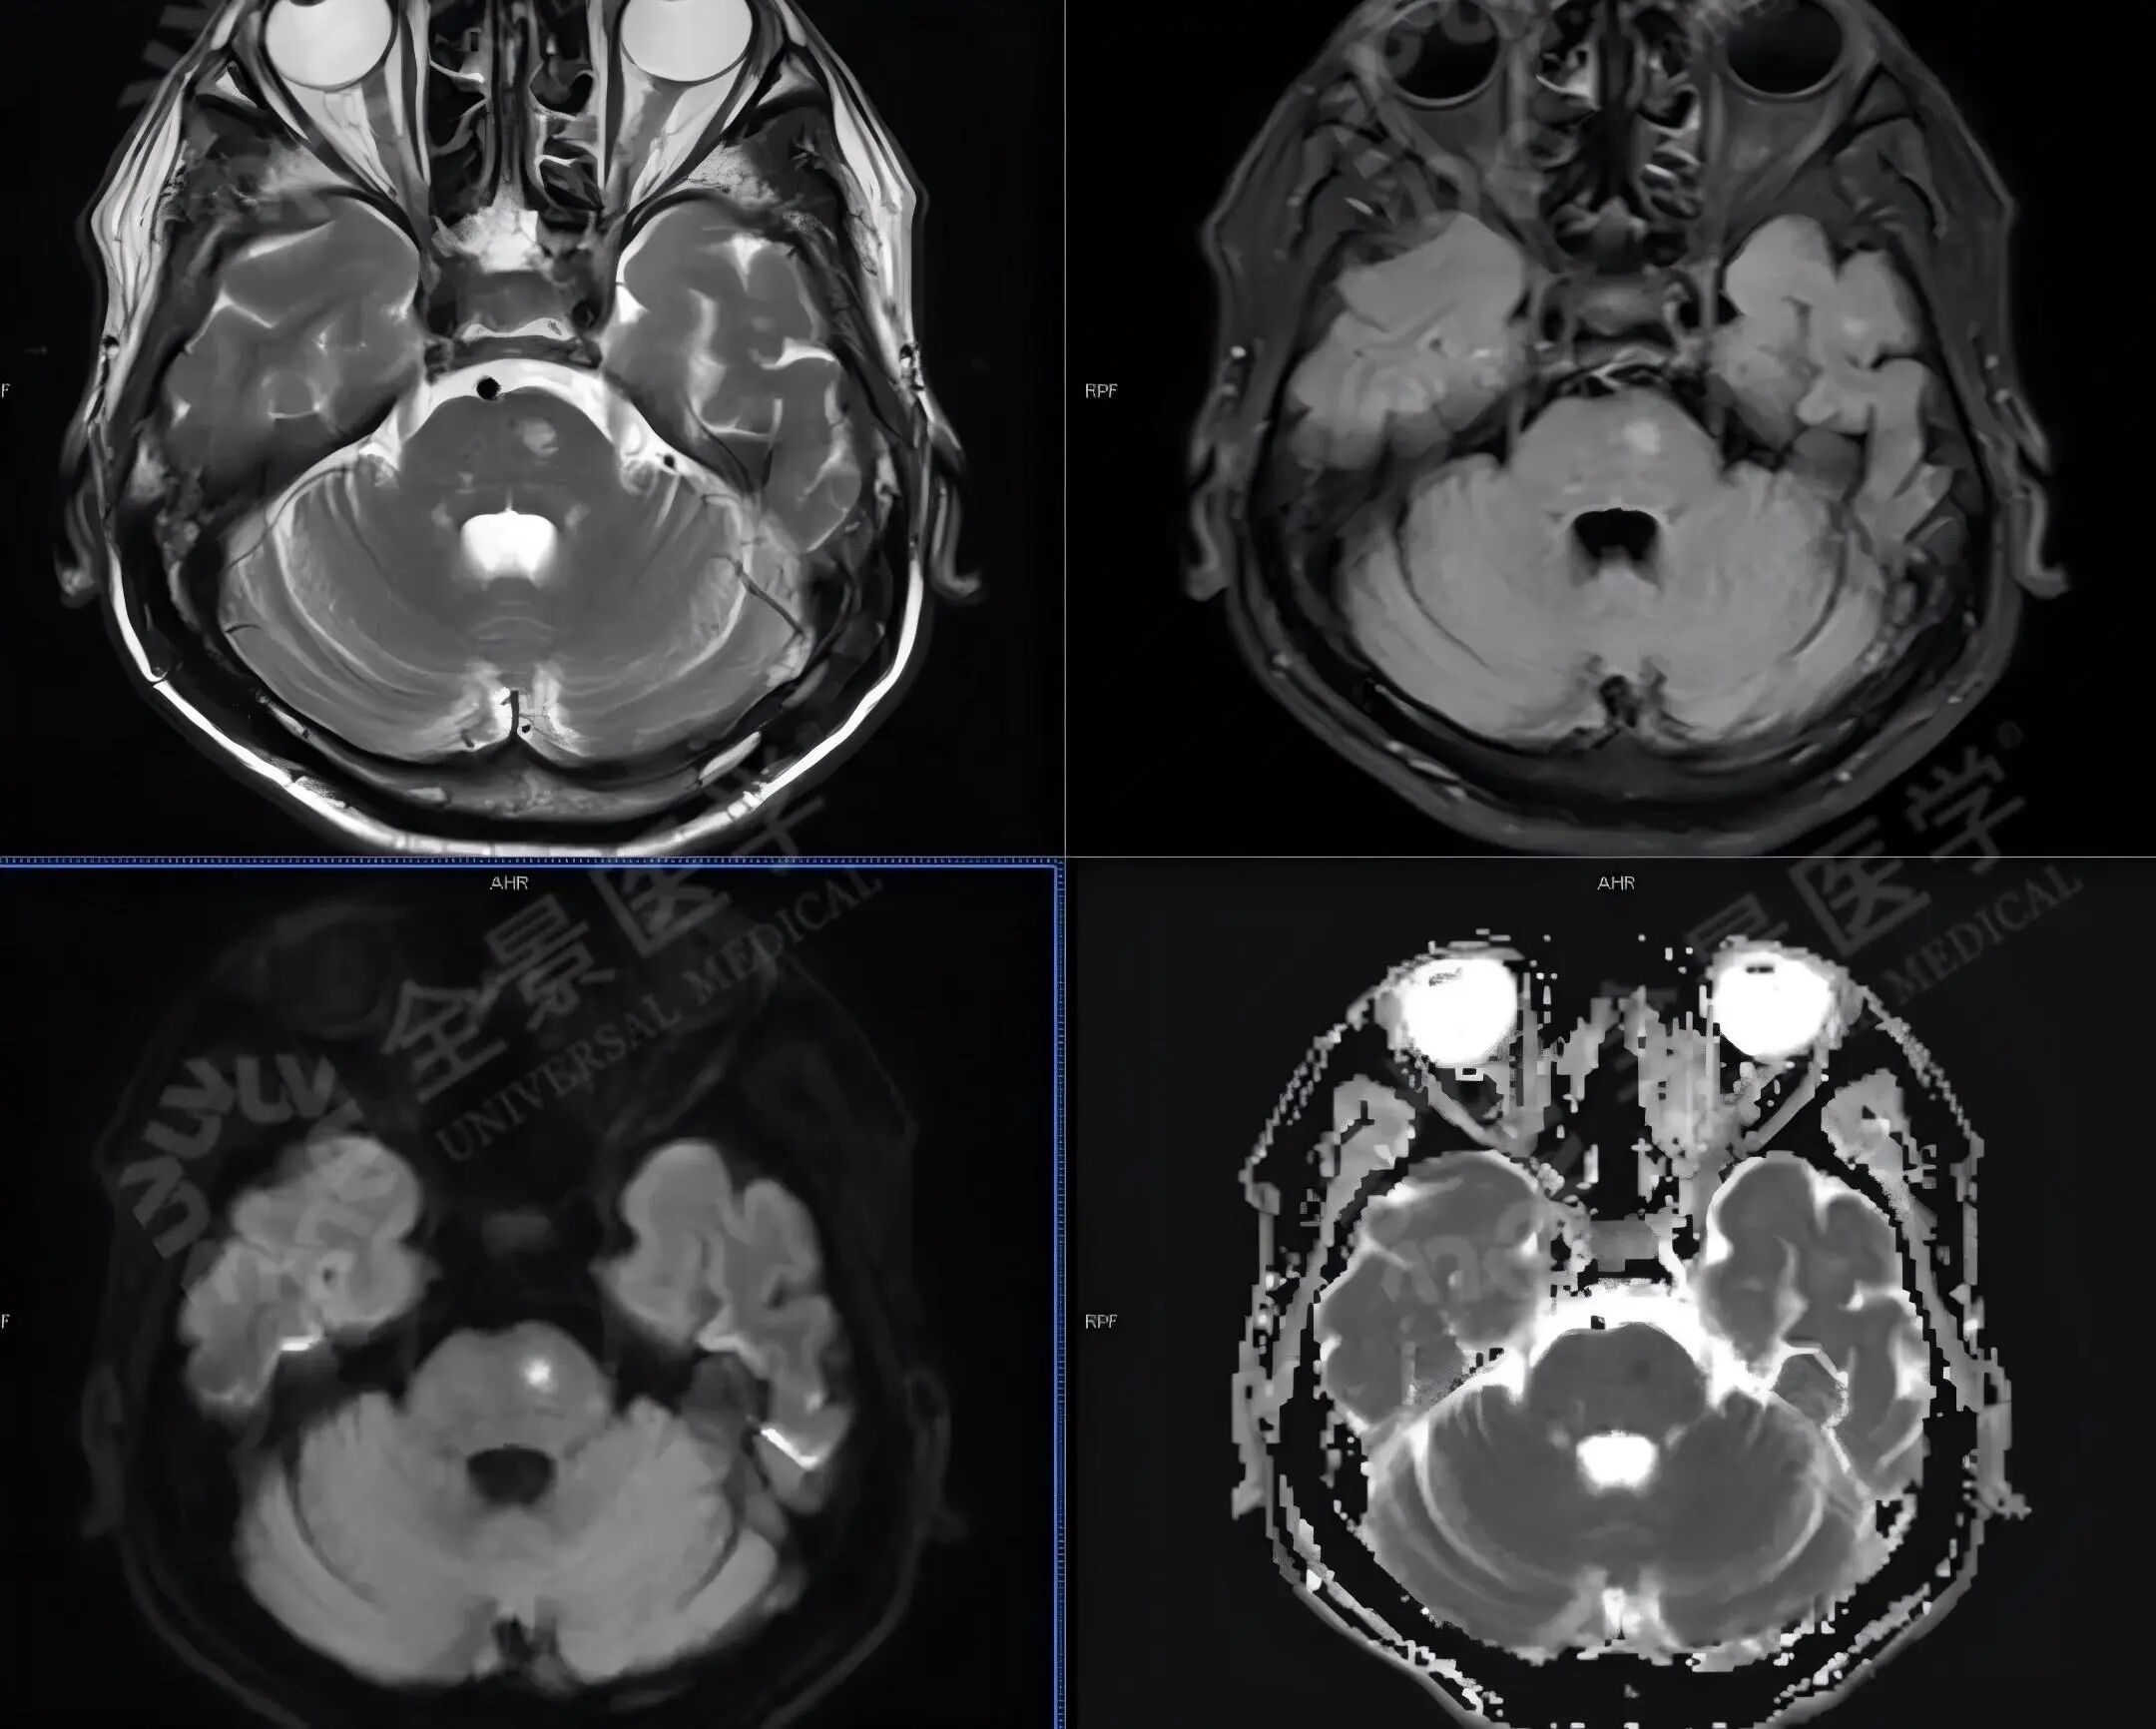

苏先生,60 岁,突感无力,休息后缓解,MR+MRA 后发现左侧桥脑急性脑梗死。